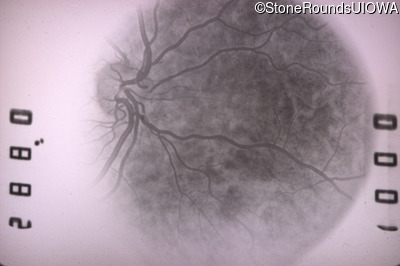

Fluorescein Angiography - Left - 20/20 -1 sc

Exemplar